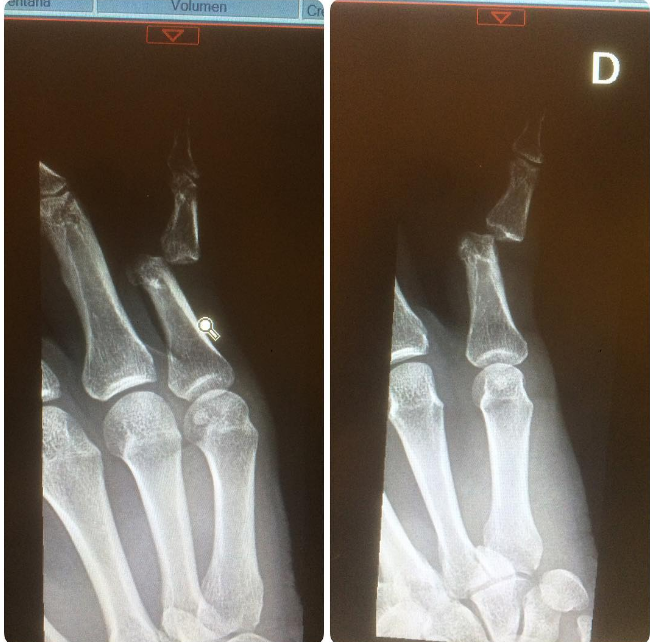

Posteriormente, el expololo de Francini Amaral, subió una radiografía donde efectivamente se puede apreciar la luxación que sufrió.